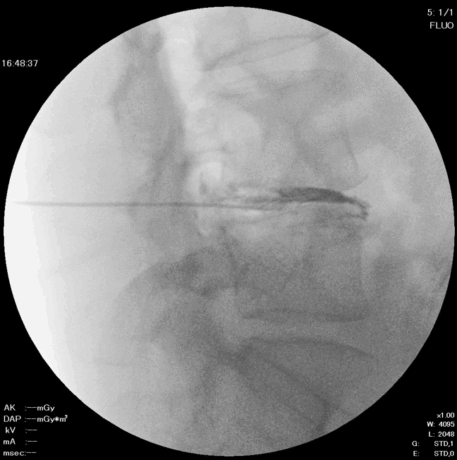

3. 髄核の一部摘出

グラスパー鉗子を用いて、椎間板内部の髄核を一部取り出します。

4. ラジオ波焼灼(アブレーション)

留置針にデバイスを挿入し、ラジオ波で焼灼を行います。

DISC-FXはDARTよりも太いデバイスのため、やや大きいヘルニアに適しています。頚椎ヘルニアの場合にはDARTが選択されます。